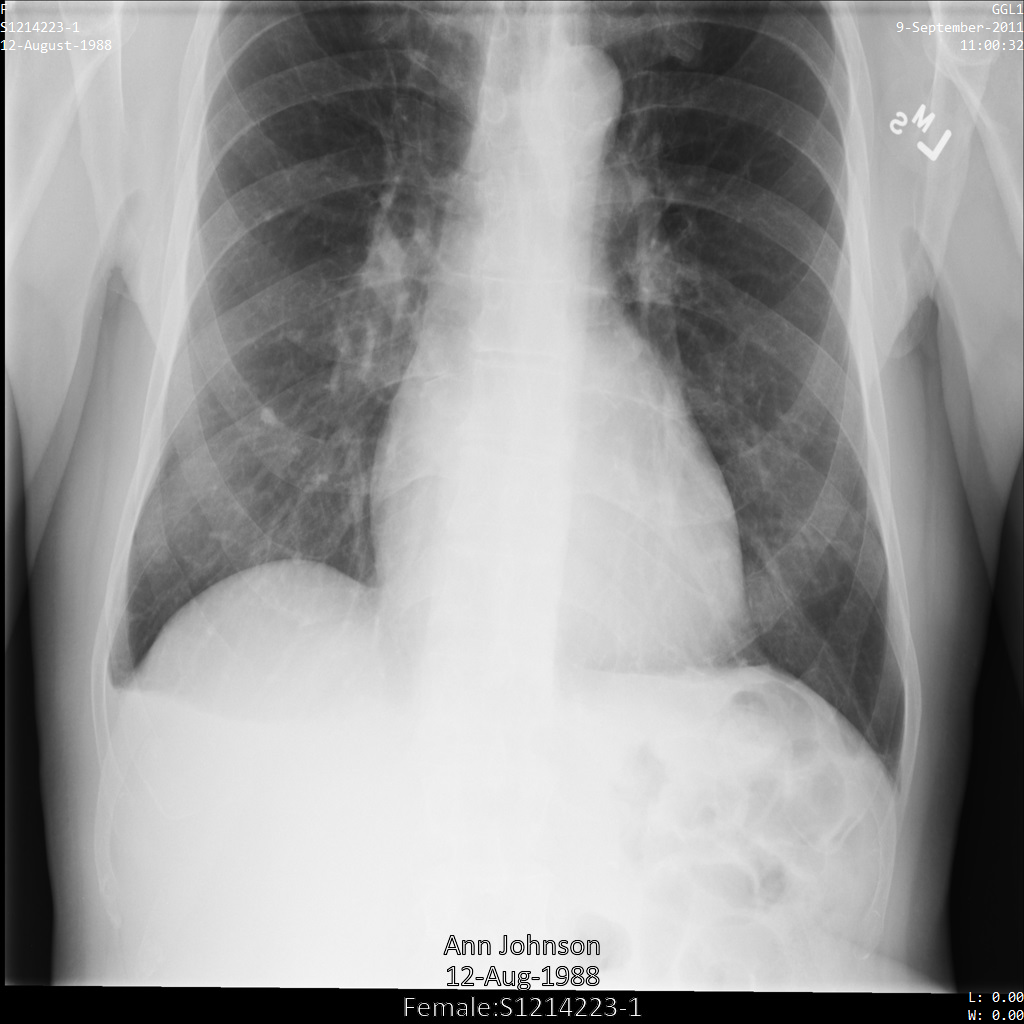

Les exemples suivants montrent comment anonymiser un ensemble de données contenant des magasins DICOM et des données DICOM à l'aide du profil de filtre de tag ATTRIBUTE_CONFIDENTIALITY_BASIC_PROFILE. Ce profil de filtre de tag supprime les tags en fonction du profil de base de la confidentialité d'attribut du standard DICOM. L'API Cloud Healthcare n'est pas entièrement conforme au profil de base de la confidentialité d'attribut. Par exemple, l'API Cloud Healthcare ne vérifie pas les restrictions de définition d'objet d'informations (IOD) lors de la sélection d'une action pour un tag.

Une fois envoyée à l'API Cloud Healthcare à l'aide du profil de filtre de tag ATTRIBUTE_CONFIDENTIALITY_BASIC_PROFILE, l'image apparaît comme suit. Les métadonnées affichées dans les angles supérieurs de l'image ont été masquées, mais les données de santé incrustées en bas de l'image reste affichées. Pour supprimer également le texte incrusté, consultez la section Masquer le texte incrusté dans les images.

dicom_attribute_confidentiality_basic_profile